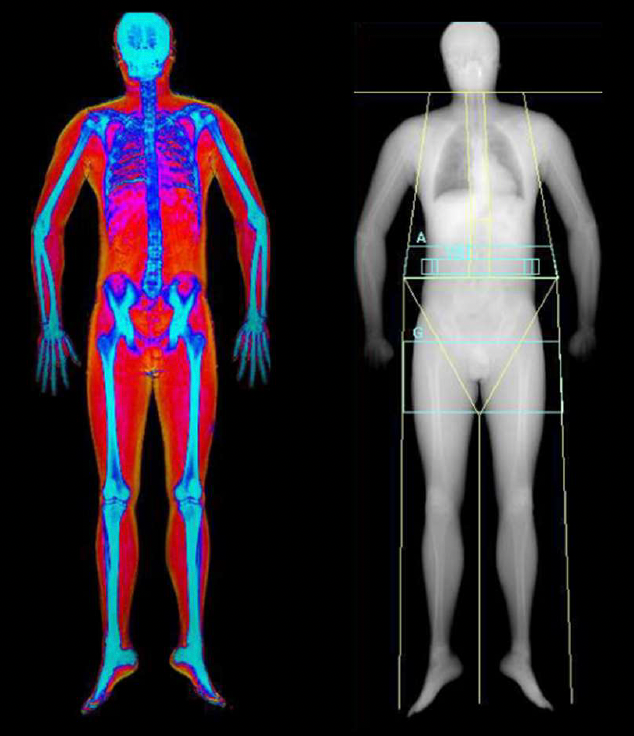

A DEXA scan (short for Dual-Energy X-ray Absorptiometry) is a simple, non-invasive scan that shows you exactly what your body is made of - fat, muscle, and bone.

Originally developed to measure bone density, DEXA has become the gold standard for body composition analysis. Unlike scales or BMI charts that only tell you how much you weigh, a DEXA scan breaks that weight down into real, meaningful data so you can understand your body on a deeper level.

Think of it as a full-body blueprint. In less than 10 minutes, you’ll get a precise, visual breakdown of your fat percentage, lean muscle mass, visceral fat (the fat stored around your organs), and bone density.